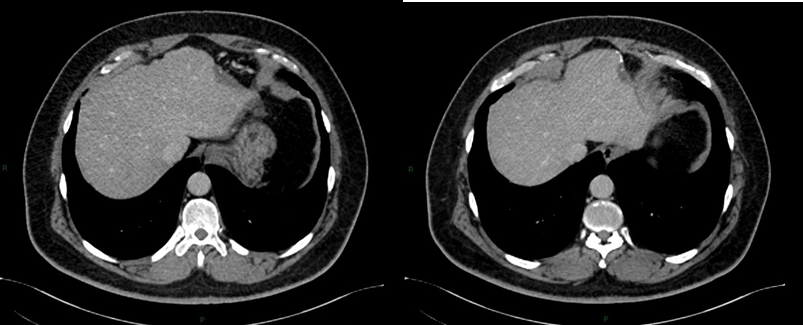

Intrahepatic splenosis shows increased enhancement on CT or MR images during the arterial phase. Performing gadoxetic acid–enhanced hepatocyte-phase MR imaging does not help because intrahepatic splenosis is hypointense during the hepatospecific phase. The MR technique involving administration of small iron oxide particles (SPIO-Endorem), which is taken up by liver and spleen reticuloendothelial cells, has proven to be effective in differentiating intra-hepatic splenosis from other lesions.14,15,18 With SPIO (superparamagnetic iron oxide) intrahepatic splenic nodes remain hyperintense.19 Noncontrast CT reveals a well circumscribed iso- or hypodense mass in the liver, while noncontrast MRI demonstrates mild-to-moderate hyperintensity on T2-weighted image and hypointensity on the T1-weighted image. A dynamic study on CT and MRI shows a slight to intense enhancement, which may be homogeneous or heterogeneous during the arterial phase but enhancement is diversely during the portal venous and equilibrium phases in different cases. Compared with the surrounding hepatic parenchyma, the lesion could reveal hypodensity and hypointensity, or hyperdensity in the arterial phase. Or it can demonstrate diminished enhancement, slight enhancement, or increased enhancement during the following phases (Figure 2 & 3).19,20

Figure 3Postoperative figures A, B, C, D and E. Computed Tomography (CT). Postoperative CT in the axial plane in the post-contrast venous phase show signs of partial resection of the liver segment II (A,B, C and D), as well as splenectomy with small implants of splenic tissue in the left subphrenic region (E).

In standard imaging techniques, such as US, CT-scan, or MRI, the hepatic splenosis may mimic adenoma, hepatocellular carcinoma, or metastatic liver neoplasms.8,21 In the imaging studies, the diagnosis was not definitive and hence the need for an invasive procedure.

The keys to diagnose intrahepatic splenosis are knowledge of splenic injury, the subcapsular location of the lesion (mostly in the left liver lobe), and the association with other hypervascular intraperitoneal lesions.22 If intrahepatic splenosis is suspected, technetium-99m–labeled red blood cell scintigraphy should be performed and represents the most specific imaging technique.8,22,23 Histology represents the gold standard for the diagnosis.8,24 Sometimes, laparoscopy is necessary for biopsy. Histologically, liver splenosis presents as nodular lesions rich in lymphoid tissue and hematopoietic cells, no hilus and its blood supply is derived from surrounding tissues and vessels (Figure 3).5,12 Due to the lack of adequate reported cases, there's no consensus on a gold standard diagnostic approach to hepatic splenosis.14